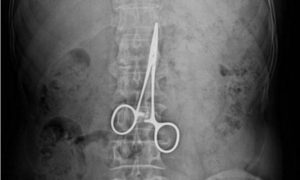

9 GODINA HIRURŠKE MAKAZE MU ŠETALE PO STOMAKU: Za sve muke kroz koje je prošao bolnica će platiti 10.000 evra!

Univerzitetska klinička bolnica (SKB) Mostar moraće da isplati A.P. (41), 10.000 evra plus kamate i troškove sudskog postupka, zbog lekarske greške tokom...